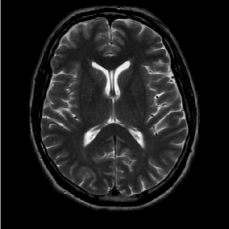

(b) FLAIT brain

Refer to caption

Figure 2: Test Images.

We turn now to test TDIHT for high dimensional signals. We test the performance of several MRI images: the Shepp-Logan phantom, FLAIT brain image, T2 Sagittal view of the lumbar spine and the circle of Willis. The first image is of size 256×256256256256\times 256, while the other are of size 512×512512512512\times 512. They are all presented in Fig. 2.

We focus on the recovery of these images from a few number of Fourier measurements. With 𝛀𝛀{\mathbf{\Omega}} set to be the undecimated Haar transform with one level of resolution (redundancy four) and 𝐃𝐃\mathbf{D} its inverse transform, we succeed to recover the phantom image using only 181818 sampled radial lines, which is only 6.5%percent6.56.5\% of the measurements. This number is only slightly larger than the number needed for GAP, relaxed ASP (RASP) and Relaxed ACoSaMP (RACoSaMP) in [10, 38]. The advantage of TDIHT over these methods is its low complexity as it requires applying only 𝐌𝐌{\mathbf{M}} and its conjugate and 𝛀𝛀{\mathbf{\Omega}} and its inverse transform while in the other algorithms a high dimensional least squares minimization problem should be solved. Note also that for AIHT and RAHTP the number of radial lines needed for recovery is 353535 and for IHT (with the decimated Haar operator with one level of resolution) we need more than 505050 radial lines.